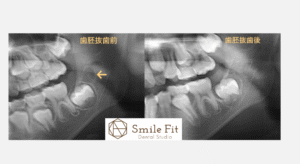

歯胚抜歯(しはいばっし)

歯胚抜歯とは?将来の歯並びを守るために知っておきたいこと|Smile Fit Dental Studio祐天寺